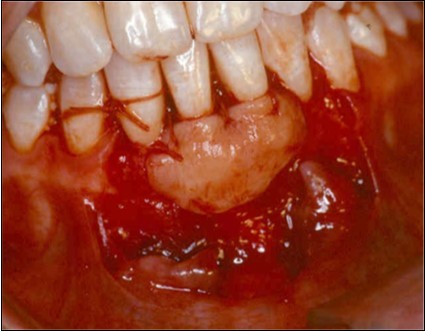

A second surgical site is created on the palate. The length of this is determined by the combines width of the teeth to be covered. The incisions are made in an anterior posterior direction. They are carried to the depth of the palatal mucosa, where they converge just short of the bone. A wedge of tissue is removed as free gingival graft, and its band of epithelium is excised by using Er:YAG laser and acute dissection with scalpel and blade 15C (Figure 4, Figure 4A). The graft is placed in the previously recipient site so that it completely covers the formerly exposed root area (Figure 5). It is then firmly sutured in place with 5-0 gut. The partial thickness, flap is positioned coronally in a manner to cover as much of the graft as possible and sutured in this position to promote maximum adaptation to ensure better healing with less chance of wound dehiscence (Figure 6). The donor site and recipient site is covered with surgical dressing and the patient is instructed in normal postsurgical management. The patient is seen on the 7th postoperative day to remove the surgical dressing and sutures. No additional dressing is necessary, and normal plaque control techniques are resumed (Figure 7)

Figure 5.Subepithelial graft sutured over exposed roots surfaces

Subepithelial graft sutured over exposed roots surfaces